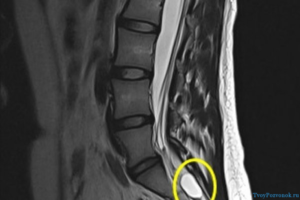

Киста пояснично-крестцового отдела на МРТ